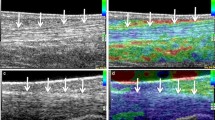

The initial results of ultrasound in fresh specimens prior to dissection showed a deterioration of image quality in both specimens used. Hence the subjective quality rating was judged moderate in the fresh specimens and excellent in the embalmed specimens. After denudation of the structures of interest, the quality in fresh specimens was judged good and in embalmed specimens excellent. These differences were related to multiple artefacts secondary to the presence of tissue gas (Fig. 1). The small gas bubbles had occurred in some areas of the specimen, other areas being spared. Nevertheless, a systematic analysis of the specimen by ultrasound was not possible. This phenomenon occurred despite the meticulous use of a method that was previously described for MR imaging for specimen conservation [1]. In contradistinction, the image quality in the embalmed specimens was excellent in all cases. There were no areas containing deposits of gas.

a Embalmed specimen: Transverse ultrasound of the flexor tendons at the palmar side of the metacarpophalangeal joints. Flexor superficialis and profundus tendons are seen (white arrows). Note the homogeneous appearance of the subcutaneous tissue (curved arrow). b Fresh specimen: Comparable image in fresh specimen. Detail of flexor tendons is less well depicted (white arrows). Also note the more heterogeneous subcutaneous tissue (curved arrow). Hyperechoic foci probably correspond to small gas deposits (short white arrows)

In our investigation we observed that the fresh specimens contained gas bubbles (Figs. 2, 6) in the soft tissues, making evaluation of underlying structures difficult. It did not seem possible to displace the gas bubbles by changing the angle of incidence or increasing transducer pressure.

In addition there appears to be an embalming effect that results in a more homogeneous appearance of the specimen, compared to fresh specimens, since after removal of skin and subcutaneous tissue the quality of embalmed specimens was still better at ultrasound (Fig. 6). This is in contradistinction to the situation with MR–anatomic correlations, where MR imaging is not adequate in embalmed specimens (M. De Maeseneer, J. Van Roy, personal observations).